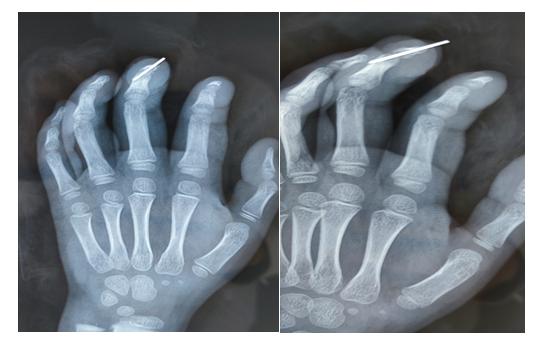

术前拍片情况:

术后14天拍片情况复查: